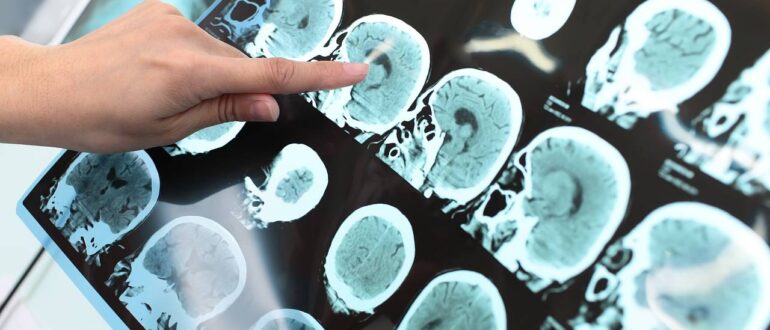

Увеличение мышечной массы и уменьшение количества висцерального жира могут существенно замедлить процессы старения мозга. К этому выводу пришли ученые, представившие свои исследования на ежегодной конференции Радиологического общества Северной…